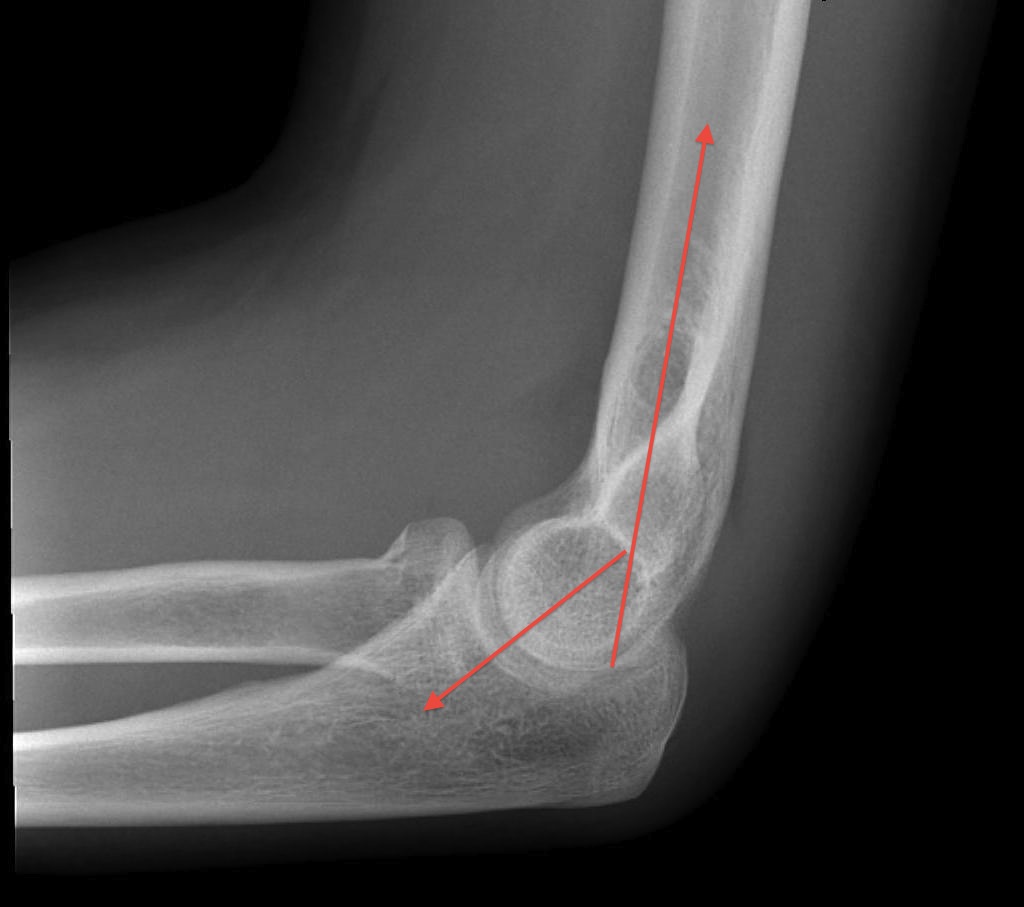

Humeroulnar joint

- hinged joint

- trochlea axis is centre of rotation

- 40o anterior angulation in sagittal plane

- trochlea 3-8o externally rotated

- 4 - 8o valgus